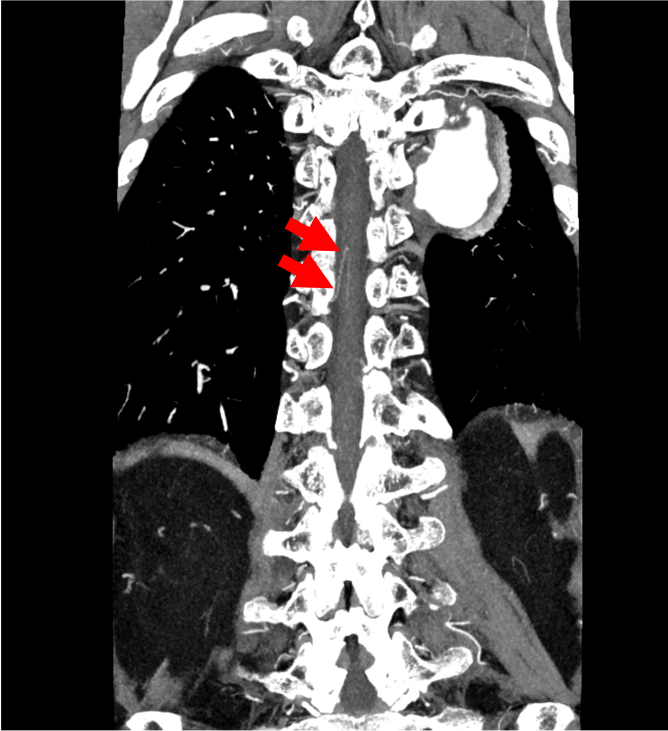

胸腹部大動脈瘤の術前検査として施行された。右第10肋間動脈から分岐し、脊柱管内右側を上行、ヘアピンカーブをなして前脊髄動脈に合流する動脈が描出され、アダムキュービッツ動脈と考えられた。

当該疾患の診断における造影CTの役割

アダムキュービッツ動脈は最も太い前根髄動脈を指し、肋間動脈や腰動脈から分岐しヘアピンカーブを描いて前脊髄動脈に合流する。第8肋間動脈から第1腰動脈から分岐することが多く、また左側から分岐することが多い。脊髄循環の維持を目的に、胸腹部大動脈瘤の術前においてはアダムキュービッツ動脈の同定が要求されることが多い。アダムキュービッツ動脈の同定においては、肋間動脈または腰動脈から分岐して脊柱管内を上行しヘアピンカーブを描いて前脊髄動脈に合流するという特徴的な形態をCT angiographyの元画像で丹念に探すことが重要である。Volume Rendering (VR) 像を作成すると全体を俯瞰できアダムキュービッツ動脈の走行の全体像を容易に認識することができる。